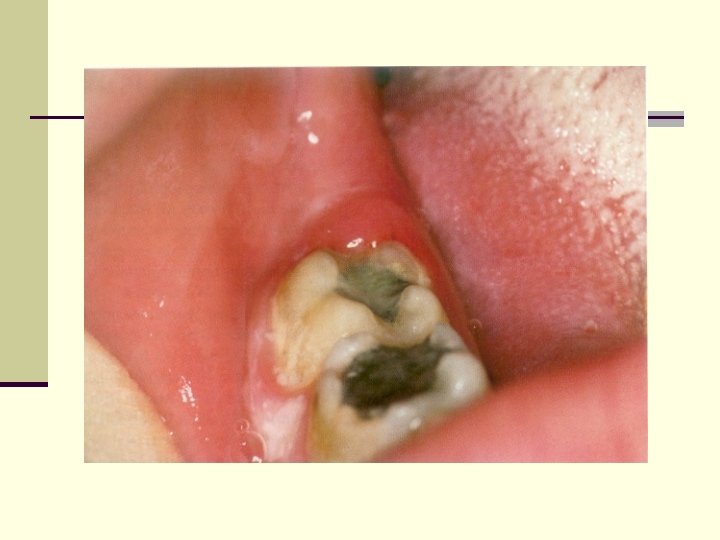

PERICORONITIS Definition n It is an acute infection which refers to inflammation of gingiva and surrounding soft tissues of an incompletely erupted tooth. n It occurs most frequently in the mandibular third molar area. n Types Acute, sub-acute or chronic.

Clinical Features Signs and Symptoms: n Markedly red, edematous suppurating lesion , extremely tender with radiating pain to the ear, throat and floor of the mouth. n Foul taste n Inability to close the jaws. n Swelling of the cheek in the region of the angle of the jaw is seen.

Acute Pericoronitis n Varying degrees of involvement of pericoronal flap as well as with systemic complications. n An influx of inflammatory fluid and cellular exudates results in an increase in bulk of the flap which interferes with complete closure of the jaws. The flap is traumatized by contact with the opposing jaw and inflammatory involvement is aggravated. n Lymphadenitis, toxic systemic complications- fever, leukocytosis and malaise.